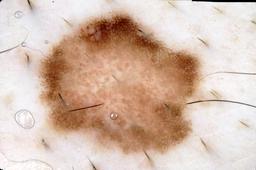

{

"age_approx": 45,

"anatom_site_general": "anterior torso",

"concomitant_biopsy": true,

"dermoscopic_type": "contact non-polarized",

"diagnosis_1": "Malignant",

"diagnosis_2": "Malignant melanocytic proliferations (Melanoma)",

"diagnosis_3": "Melanoma, NOS",

"diagnosis_confirm_type": "histopathology",

"image_type": "dermoscopic",

"lesion_id": "IL_3573306",

"melanocytic": true,

"patient_id": "IP_7383530",

"sex": "male"

}